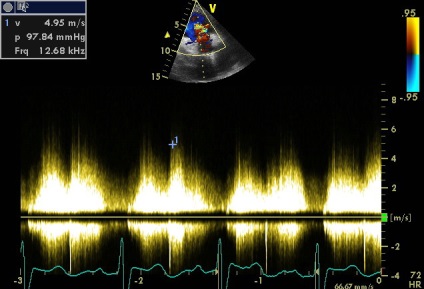

Sinus Valsalva - egy zseb-szerű szerkezet határolt szálas gyűrűt szelepcsappantyú, és az illető semiiunaris aorta fal, annak felső határa - sino-csöves csatlakozás. A falakat a két szinusz van a szája, a jobb és a bal koroanrnyh artériák, és hívják a jobb és a bal koszorúér sinus, és a maradék egyharmad - a nem koszorúér. A beteg egy diszkontinuitás az aneurizma a jobb coronaria sinus Valsalva (ünnepelte gyakrabban), mint látható parastrenalnyh szakaszok rövid és hosszú távú (egy lejtőn) tengelyeken. Számos egyéb, kevésbé gyakori aneurizma orrmelléküregek, még kevésbé egyidejűleg 2 vagy 3 (nem tévesztendő össze egy egyszerű kiterjesztése aortagyök szintjén az orrmelléküregek, ellentétben, amelyek továbbra is legyen tarsoly alakú kiemelkedés a fal, mint a mi beteg). A formáció egy ilyen aneurizma egy patológiás állapottal vegyületet struktúrák bázis szelep szórólapok és aorta fal. Fistulák (kóros anasztomózis) a szinuszok szintet, és anélkül, aneurizma (pl, amely különféle fertőző endocarditis). Csakúgy, mint az aneurizma nem bonyolítja egy hosszú szünet (és általában nem, hogy klinikailag). A rés a kialakulását a sipoly kiváltható trauma, szívbelhártya-gyulladás, magas vérnyomás, stb de néha spontán. A szünet alakul súlyos volumen túlterhelés, olyan funkciókkal, hemodinamikus megnyilvánulások, attól függően, hogy melyik kamrában visszaáll az aortából. Ebben az esetben, a reset határozzuk meg a jobb kamrai kiáramlási traktus (2. típusú), egy jelentős növekedést véráramlást a bal kamrai kiáramlási traktus (disztálisan a sipoly, miközben a szisztémás keringésbe csökken). Drámaian megnövekedett a nyomás a jobb kamra (amint azt a gradiens tricuspidalis regurgitáció + jelei megnövekedett nyomás a jobb pitvarban). De pulmonális sávval egy reflexszerűen hipovolémia, amíg részlegesen „védett” (görcs) az ilyen akut volumen túlterhelés (fokozott jelei rezisztencia lehet számítani). A helyzet sürgető, és előírja szívsebészet.

áramoltassuk a jobb kamrai kiáramlási traktus (2-es típusú)

5. Nézzük számítani a megnövekedett ellenállása az ágak a tüdő artéria

5. Nézzük számítani a megnövekedett ellenállása az ágak a tüdő artéria

PVR lehet, például, számolni, és így

Vannak más képletek jóváhagyott különböző forgatókönyvek hemodinamikai